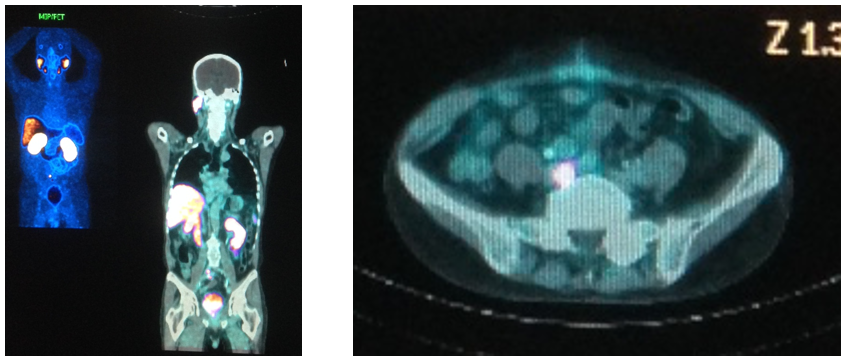

• PET-TC PSMA

– LN ilíaco comum E 1,4cm (SUV=10,9), ilíaco comum D 1cm (SUV=6,7)

– 5 LNs mesentérico inferior e retais superiores até 0,9cm (SUV=3,1)

– Estabilidade de linfonodos

– Lesão óssea esclerótica 1,3 cm ísquio E (SUV=3,0)